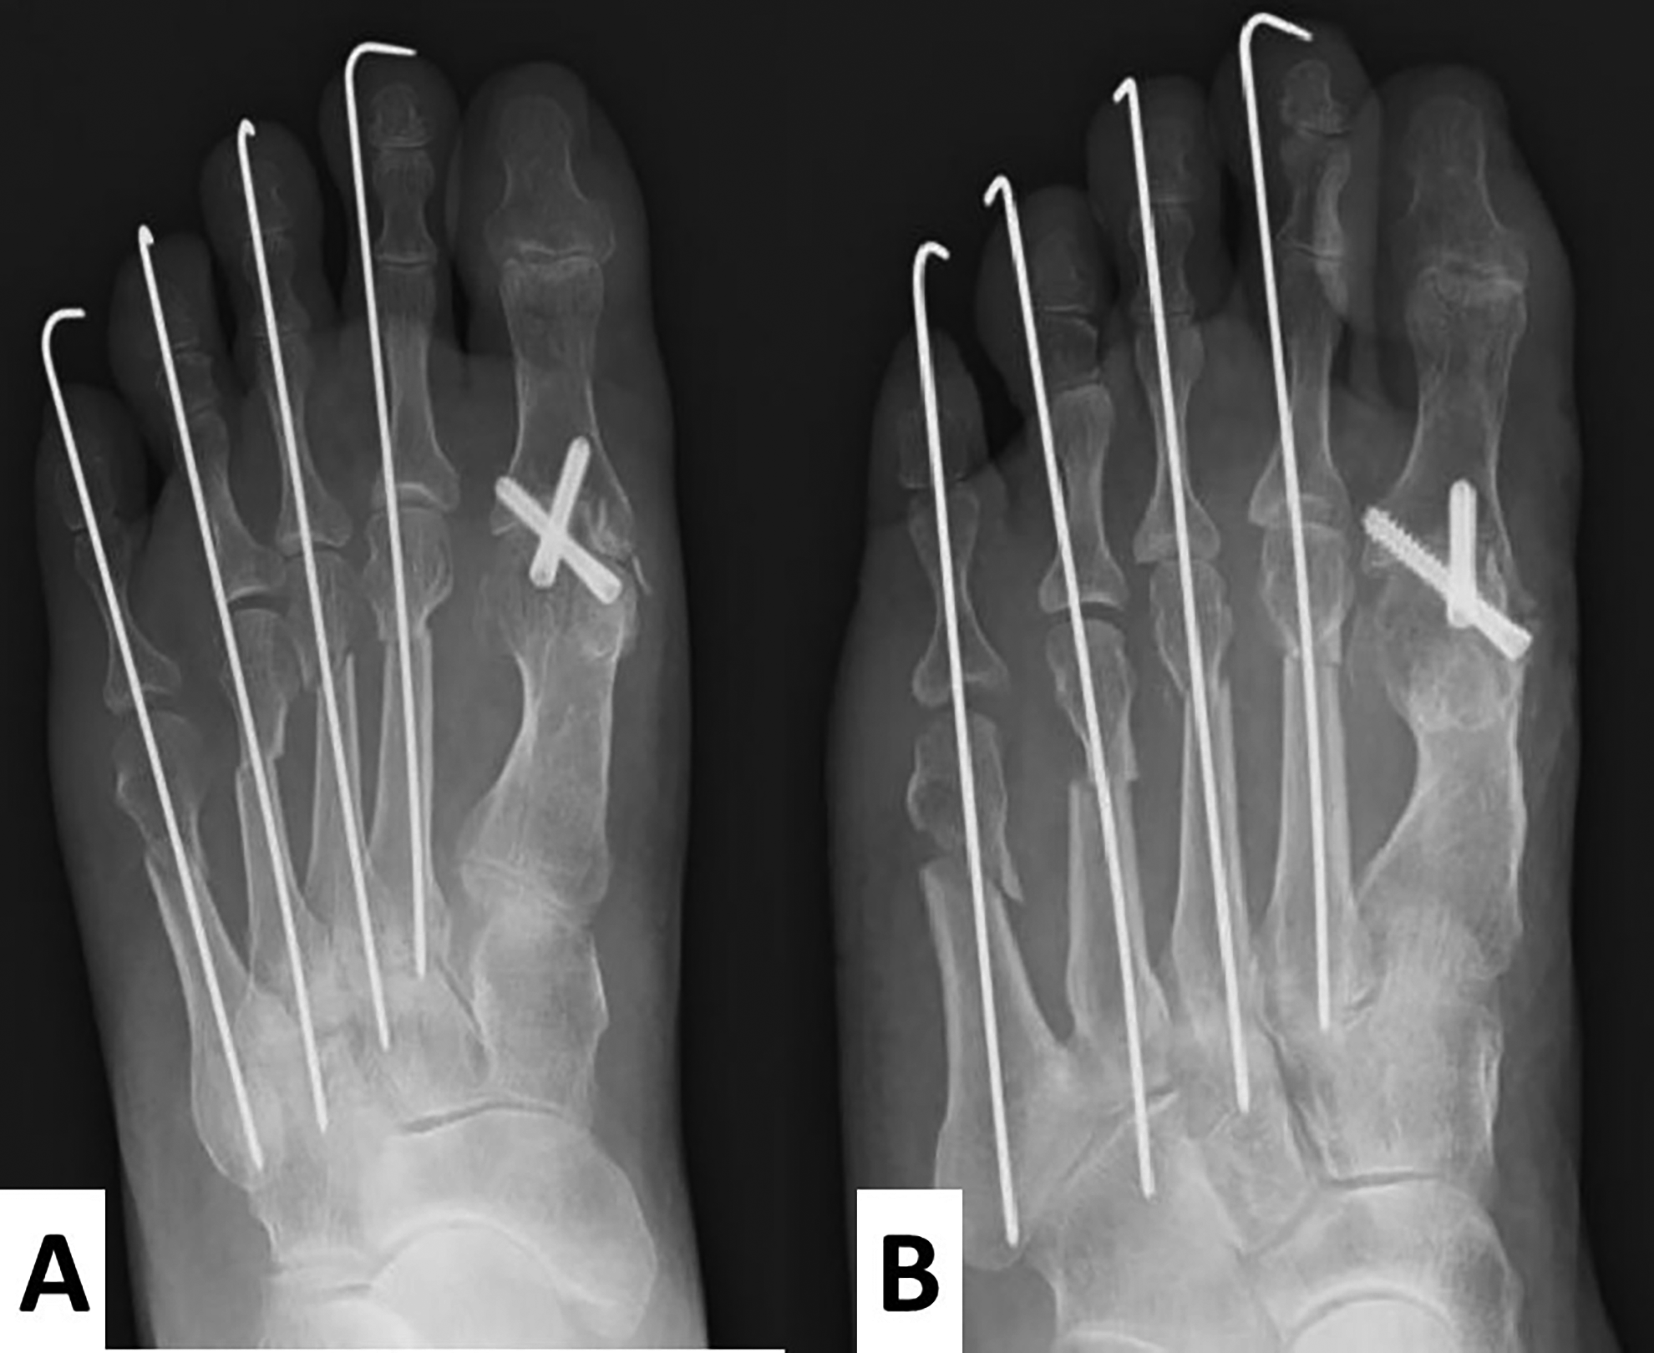

The hallux valgus angle was fixed at 0°, and the first proximal phalanx axis was dorsally fixed at 15° to the metatarsal bone axis. Two full-thread Acutrak® screws (Nihon Medical Next Co. Ltd, Tokyo, Japan) were inserted at the fixed position in a crisscross fashion. For the lesser toes, a shortening oblique osteotomy was performed (Figure 5A and B). The postoperative radiographs showed that M1M2A was 6° and HVA was 0° (Figure 5A).

A cup and cone reamer are used to preserve the length of the hallux as much as possible. The hallux valgus angle is fixed at 0°, and the 1st proximal phalanx is dorsally fixed at 15° to the metatarsal bone. M1M2A shows 6°. For the lesser toes, a shortening oblique osteotomy is performed (A, anteroposterior view; B, oblique view).

Temporal fixation of the lesser toes with Kirchner wires (1.2 mm in diameter) was performed, and then the wires were removed after three weeks. Arch support was applied, and full weight gait exercise was performed.